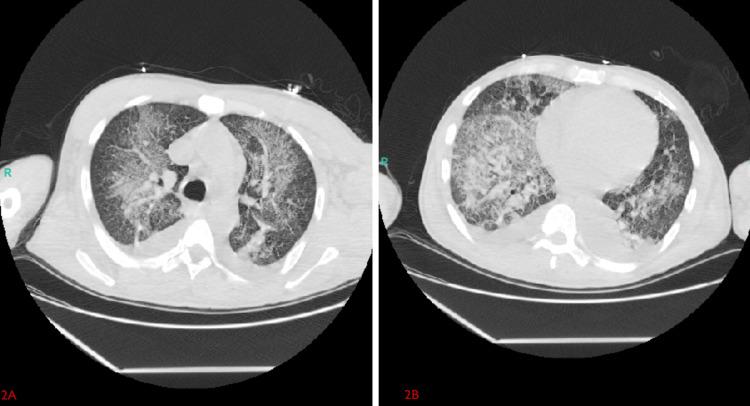

Diffuse alveolar hemorrhage (DAH) is a rare but life-threatening pulmonary condition characterized by bleeding into the alveolar spaces, most commonly associated with autoimmune or vasculitic disorders. However, drug-induced DAH, particularly from the inhalation of substances like cocaine and fentanyl, is an emerging concern. A 37-year-old homeless male with a history of intravenous and inhaled polysubstance abuse was found unresponsive and treated with intranasal naloxone for presumed opioid overdose. Upon arrival, he exhibited respiratory distress, pink frothy sputum, severe hypoxemia, and acute renal failure with refractory hyperkalemia. Imaging revealed diffuse bilateral alveolar infiltrates, and large volumes of bright red blood were suctioned during intubation. Bronchoalveolar lavage confirmed DAH with numerous hemosiderin-laden macrophages. Infectious and autoimmune workups were negative, while urine toxicology was positive for both fentanyl and cocaine. Management included lung-protective mechanical ventilation, high-dose corticosteroids, and continuous renal replacement therapy, with clinical improvement and successful extubation after ten days. This case underscores the importance of considering drug-induced DAH in patients with acute respiratory failure and polysubstance use, even in the absence of hemoptysis.

弥漫性肺泡出血(DAH)是一种罕见但危及生命的肺部疾病,其特征是血液渗入肺泡腔,最常见于自身免疫性或血管炎疾病。然而,药物性DAH,尤其是吸入可卡因和芬太尼等物质引起的,正成为一个新的关注点。一名37岁有静脉注射和吸入多种药物滥用史的无家可归男性被发现无反应,因疑似阿片类药物过量接受了鼻内纳洛酮治疗。到达医院时,他表现出呼吸窘迫、粉红色泡沫痰、严重低氧血症以及伴有难治性高钾血症的急性肾衰竭。影像学检查显示双侧弥漫性肺泡浸润,插管时吸出大量鲜红色血液。支气管肺泡灌洗证实为DAH,可见大量含铁血黄素巨噬细胞。感染性和自身免疫性检查均为阴性,而尿液毒理学检查显示芬太尼和可卡因均呈阳性。治疗措施包括肺保护性机械通气、大剂量皮质类固醇以及持续肾脏替代治疗,患者在十天后临床症状改善并成功拔管。该病例强调了在急性呼吸衰竭和使用多种药物的患者中,即使没有咯血,也需考虑药物性DAH的重要性。